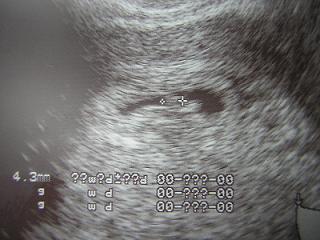

sziszitündi: Én is ezt a vitamint szedem, de én megkérdeztem a gyógyszertárban és ott még ajánlották mellé a folsavat. Most reggel egy szem folsavat szedek, este meg a vitamint. Én is gondolkodtam, hogy a héten csinálok még egy tesztet, de hétfőn megyek uh-ra, úgyhigy még gondolkozom.